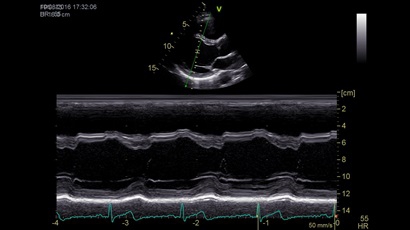

GE VIVID IQ - это передовая портативная система ультразвуковой диагностики, специально разработанная для обеспечения высокого качества образов и мобильности. Благодаря своим компактным размерам и легкому весу, VIVID IQ легко переносится и позволяет проводить УЗИ исследования в различных местах, включая комнаты пациентов, отделения скорой помощи и операционные.

GE VIVID IQ – это ультрасовременный, выполненный в виде ноутбука УЗИ сканер с самым передовым техническим оснащением для проведения диагностических обследований сердечно-сосудистой системы человека. Его особенно оценят бригады скорой помощи из-за малого веса всего 4,5 кг., удобства переноски, а также быстрого выхода из состояния сна для начала работ.

Анатомический М-режим:

Да

M-режим:

• Сенсорный экран 15.6" высокого разрешения.

• Анатомический М-режим (АММ).

• Криволинейный анатомический М-режим (CAMM).